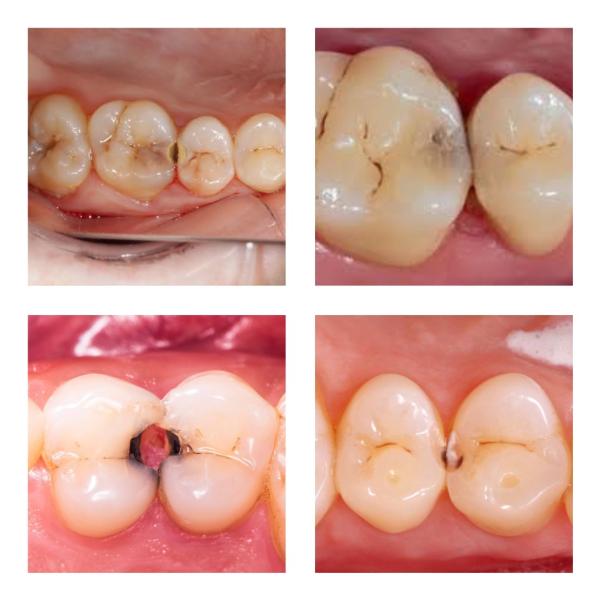

🥲Почему зубы «гниют» изнутри?

Часто с такой проблемой приходят пациенты на прием. А также с фразами «здоровый зуб быстро сгнил/сломался/начал крошиться»

⏬А всему виной он — контактный кариес. Ещё его называют скрытым. Так от чего он скрывается?

⭕️У каждого жевательного зуба есть 5 поверхностей: щечная (вестибулярная), язычная(небная), жевательная и 2 контактные, которыми они соприкасаются с соседними зубами. У резцов и клыков такие же, кроме жевательной

‼️Но зубная щетка не очищает контактные ...